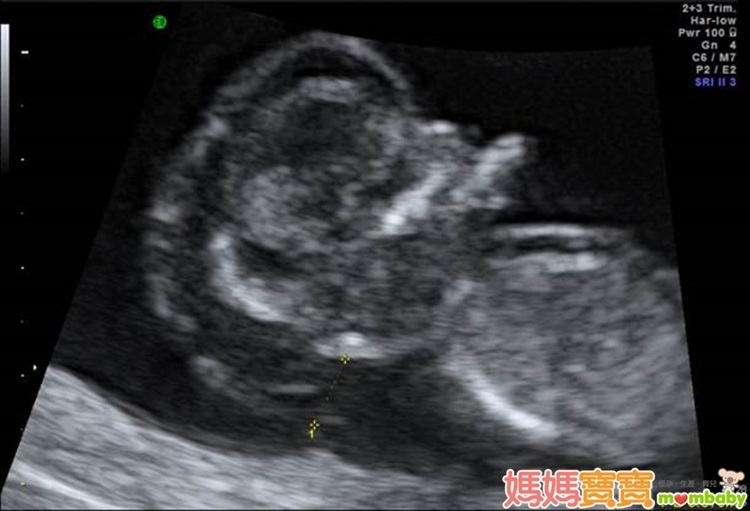

利用高解析度的超音波來檢查胎兒頸部透明帶厚度,以確認胎兒是否具備染色體或構造異常等疑慮,進而接受更進一步的評估,正是這個產檢項目的宗旨。頸部透明帶的測量部位,為胎兒頸椎表皮與表皮底下軟組織的間隙,之所以會發展這樣的篩檢方式,是因為藉由以往的臨床經驗中逐漸得知,染色體與器官構造異常的胎兒,頸部透明帶似乎皆有變厚的傾向,例如唐氏症、透纳氏症候群、先天性心臟病等,這些疾病往往合併胎兒膠原組織組成改變,或淋巴及心血管循環出現異常,進而導致頸部透明帶變得較厚;因此,醫界便開始利用這個現象來回推檢測,觀察頸部透明帶較厚的胎兒是否有較高機率發生異狀,才會演變為現今的胎兒頸部透明帶篩檢。

頸部透明帶的檢查週數為懷孕第11週~第13週又6天之間,有些準媽媽可能會以月經週期來推算懷孕週數,但如果忘了最後一次的月經日期或平常月經不規則的孕婦,醫師會利用超音波來測量胎兒的頭臀徑(頭到臀部的長度,也就是胎兒坐姿高度),若頭臀徑介於36~84公厘之間,也達到適合檢查頸部透明帶的標準。

檢查胎兒頸部透明帶之前,除了先確定懷孕週數之外,還須將膀胱內的小便排空,以免影響篩檢結果,其餘則沒有嚴格限制,也不必刻意空腹。不過,頸部透明帶的檢查時間會根據胎兒姿勢而有所變化,若胎兒姿勢恰巧可讓超音波順利照到重點部位,大概10多分鐘就可完成;但如果姿勢不好,很有可能會檢查30分鐘到1小時,準媽媽甚至需要適時下床走動或擇日安排時間重新執行。